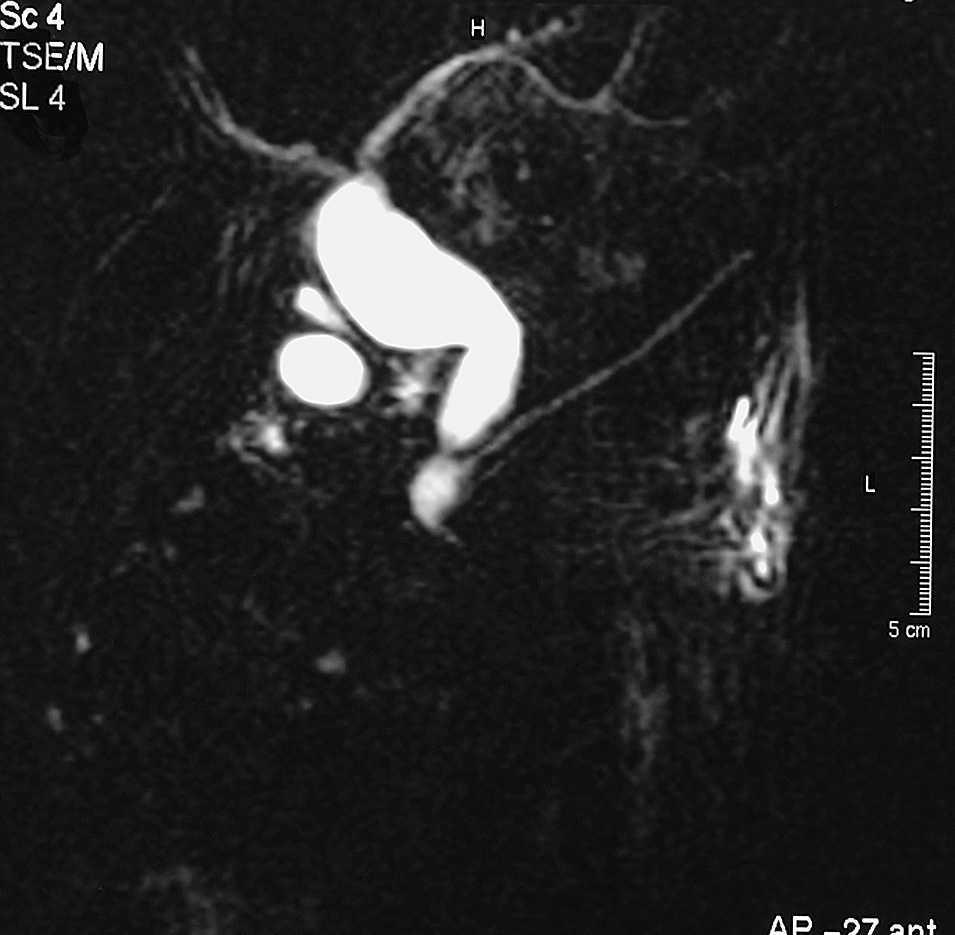

ResultadosEn la tabla 1 se resumen los resultados obtenidos. De los 18 casos registrados, 12 pacientes eran mujeres y 6, varones. La media de edad de aparición de los síntomas fue 45,8 años. La forma de presentación más frecuente fue dolor abdominal (13 casos, 72,2%). En 7 casos (38,8%) la presentación fue en forma de colangitis. Hay que destacar que el caso de adenocarcinoma se inició como hemorragia digestiva alta. El método diagnóstico predominante fue la ecografía abdominal. Hay que destacar que en los casos iniciales de la serie hay un predominio de estudio por colangiografía retrógrada endoscópica, mientras que en los casos más recientes, esta técnica ha quedado en desuso, en beneficio del estudio por colangiorresonancia magnética (fig. 2). En cuanto a los tipos de quiste, hay un predominio de quistes tipo I. El segundo tipo más frecuente es el tipo V o enfermedad de Caroli (fig. 3). En nuestra serie, no hemos registrado ningún caso de tipo III o coledococele. En los 9 casos de quiste tipo I se practicó exéresis total del quiste, colecistectomía y hepatoyeyunostomía en Y de Roux. El único caso tipo II se trató de modo similar, es decir, mediante exéresis del divertículo supraduodenal, colecistectomía y hepatoyeyunostomía. En los 3 casos con quiste tipo IVa se practicó colecistectomía y hepatectomía izquierda, con resección de la vía biliar y hepatoyeyunostomía sobre el conducto hepático derecho.

Fig. 2. Imagen de colangiografía por resonancia magnética de quiste de colédoco tipo I.